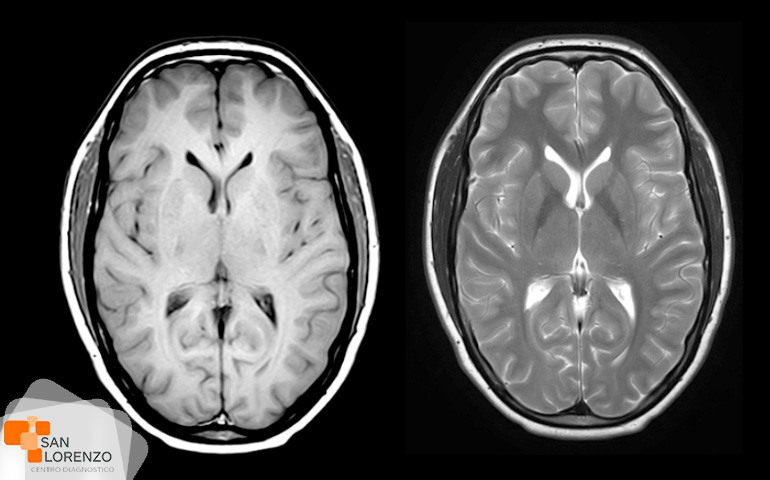

Cuando su médico especialista requiera una mejor visualización de los órganos, o estructuras internas normales o con lesiones, puede solicitar su examen con medio de contraste, éstos son sustancias indispensables para distinguir con mayor claridad áreas del cuerpo o tejidos circundantes que ayuden a diagnosticar condiciones médicas relacionadas con órganos específicos, vasos sanguíneos, o tejidos.

Frente a este requerimiento de su médico, hay que tener en cuenta que los contrastes endovenosos yodados, (usados en las TAC), o los paramagnéticos (usados en las Resonancias), pueden producir alergias o interferir en la función renal en algunos pacientes, como por ejemplo: pacientes monorrenos, con antecedentes de enfermedad renal obstructiva o cuya patología de base pueda implicar compromiso renal secundario; diabetes mellitus, mieloma múltiple, lupus e insuficiencia cardíaca, por lo tanto, en esos casos, todo examen imagenológico que requiera de contraste necesita contar previamente con un examen de creatinina.

Algunos de los exámenes relacionados con medios de contraste son: Angiotac, Urotac, TAC de abdomen y pelvis, TAC de cerebro en lo que se solicite contraste, y todas aquellas Resonancias magnéticas contrastadas.

Todos los exámenes de RM, TAC que requieran contraste tal como los mencionados anteriormente: Angiotac, Urotac, TAC de abdomen y pelvis, TAC de cerebro en lo que se solicite contraste y todas aquellas Resonancias magnéticas contrastadas.